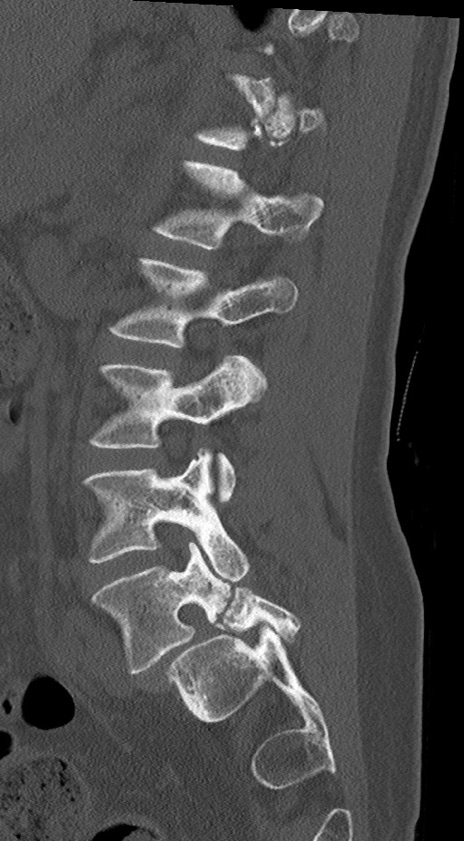

【整形】TIPS症例4 腰椎CT(矢状断像)

腰椎CT

冠状断像